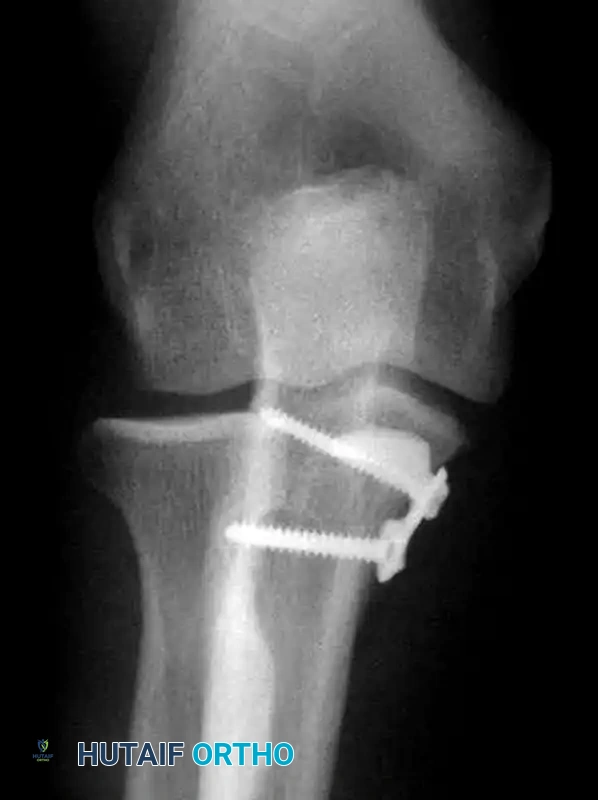

• Fixation: Anteromedial buttress plate.

3. Buttress Plating: Essential for anteromedial facet fractures to resist the shear forces of the distal humerus.

A distinct type of coronoid fracture, the fracture of the anteromedial facet, occurs from a varus force to the elbow combined with an axial load. This mechanism shears off the anteromedial rim of the coronoid and invariably ruptures the lateral collateral ligament (LCL) complex.

If left untreated, this injury results in posteromedial rotatory instability (PMRI). The ulna subluxates posteromedially, leading to rapid, catastrophic wear of the medial radiocapitellar joint and ulnohumeral arthrosis.

Surgical Warning: The sublime tubercle may be involved in anteromedial facet fractures. However, the AMCL often remains attached to the fractured fragment. Therefore, repairing the fracture effectively restores medial stability.

Treatment necessitates an aggressive surgical approach. Repair of the lateral collateral ligament and Open Reduction and Internal Fixation (ORIF) of the coronoid are strictly recommended. Fixation is best achieved using a contoured anteromedial buttress plate applied through a medial approach, supporting the fragment against the varus shear forces.

Image